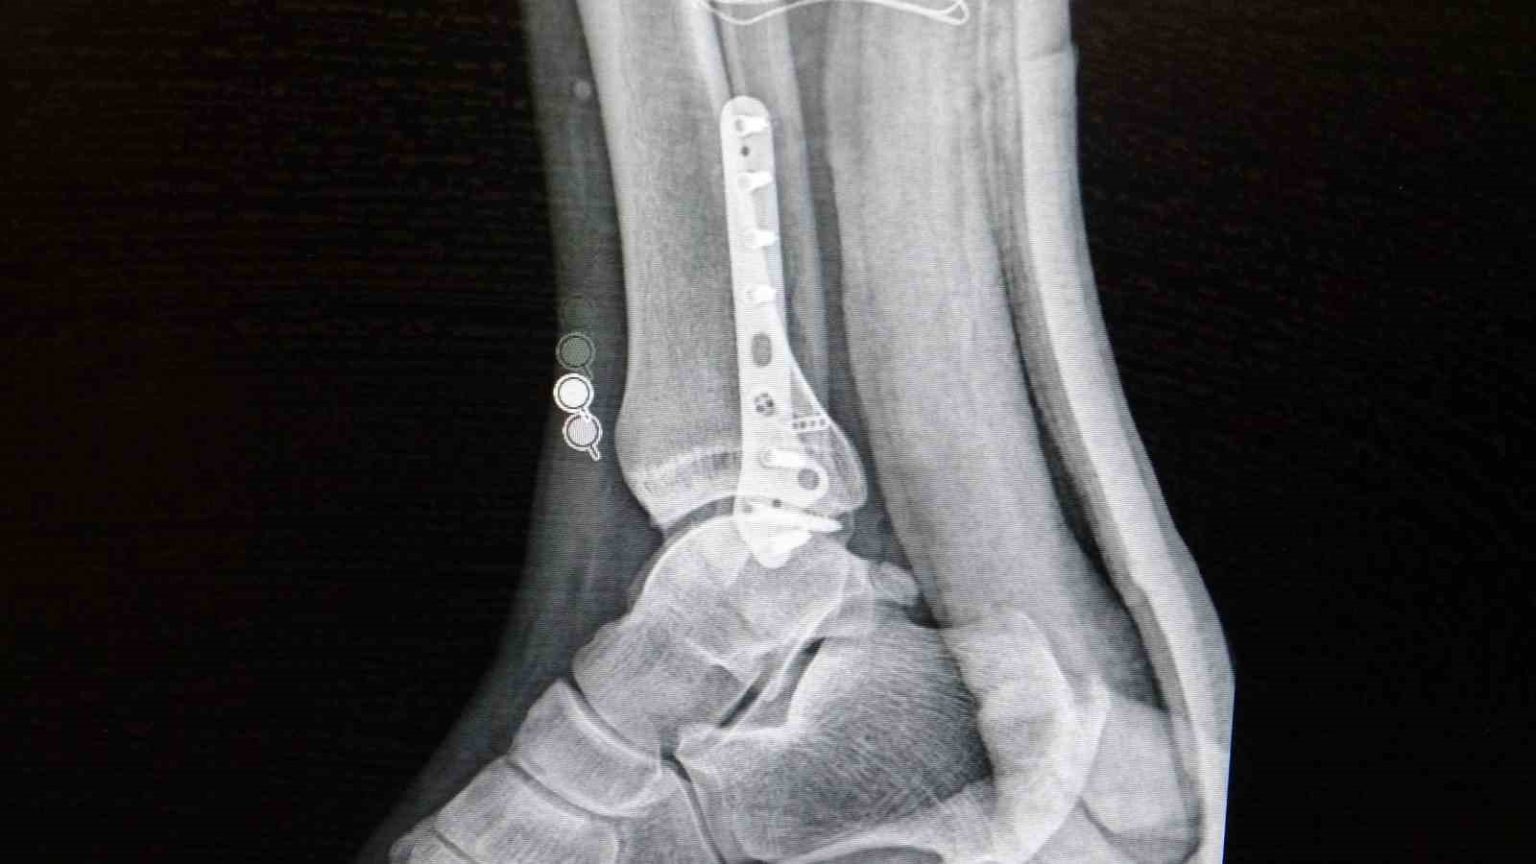

Ortopedi polikliniklerine en sık ayak bileği, diz ve omuz yaralanmalarıyla başvurulduğunu belirten Demirbaş, futbol nedeniyle yaralanma oranlarının da ilk sırada yer aldığını söyledi. Konuya ilişkin Demirbaş, “Futbolda menisküs yırtıkları, ön çapraz bağ yırtıkları, iç ve dış yan bağ yaralanmaları, aşil tendon kopmaları ve ayak bileği bağ yaralanmaları çok sık görülüyor. Ayrıca spora bağlı kırıklar da önemli bir yer tutuyor” ifadelerini kullandı.